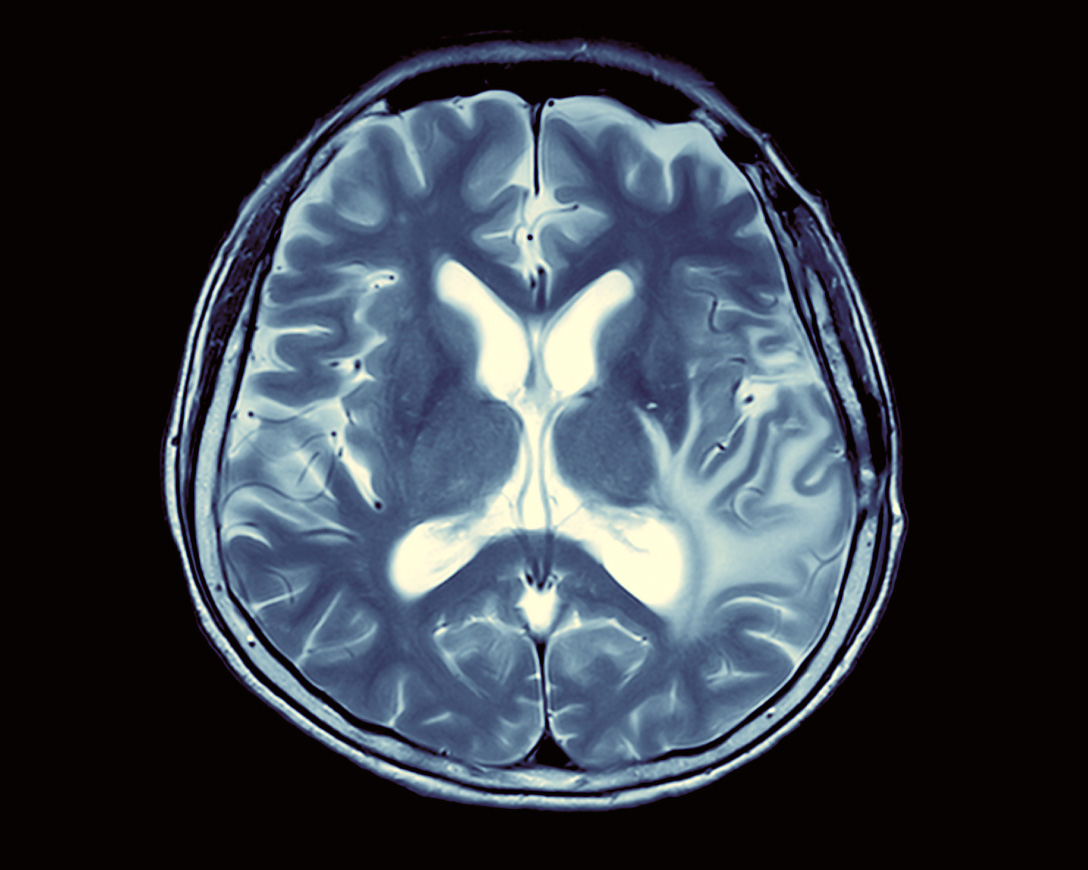

Nuclear medicine is one of the modern areas of diagnostics and treatment using radioactive isotopes. The rays emitted by the isotope highlight those variations in the organ function, which are practically impossible to detect in any other way. With such a diagnosis, it is possible to identify oncological diseases early, allowing successful treatment. The global market for nuclear medicine services is estimated at $80 billion. It is projected to grow to $300 billion in the next six years.

Nuclear medicine includes radiation and radionuclide therapy aimed at destroying cancer cells. Radiopharmaceuticals have a short and minimally harmful half-life to humans. With the latest developments in radiosurgery, for example, the cyber-blade, it is possible to remove a hard-to-reach tumor (even inside the brain) and its metastases without open surgery. Rosatom has extensive experience in working with radioactive isotopes. Therefore the state corporation is involved in developing radiopharmaceuticals, radiotherapy complexes and is working on the creation of nuclear medicine centers in Russia.